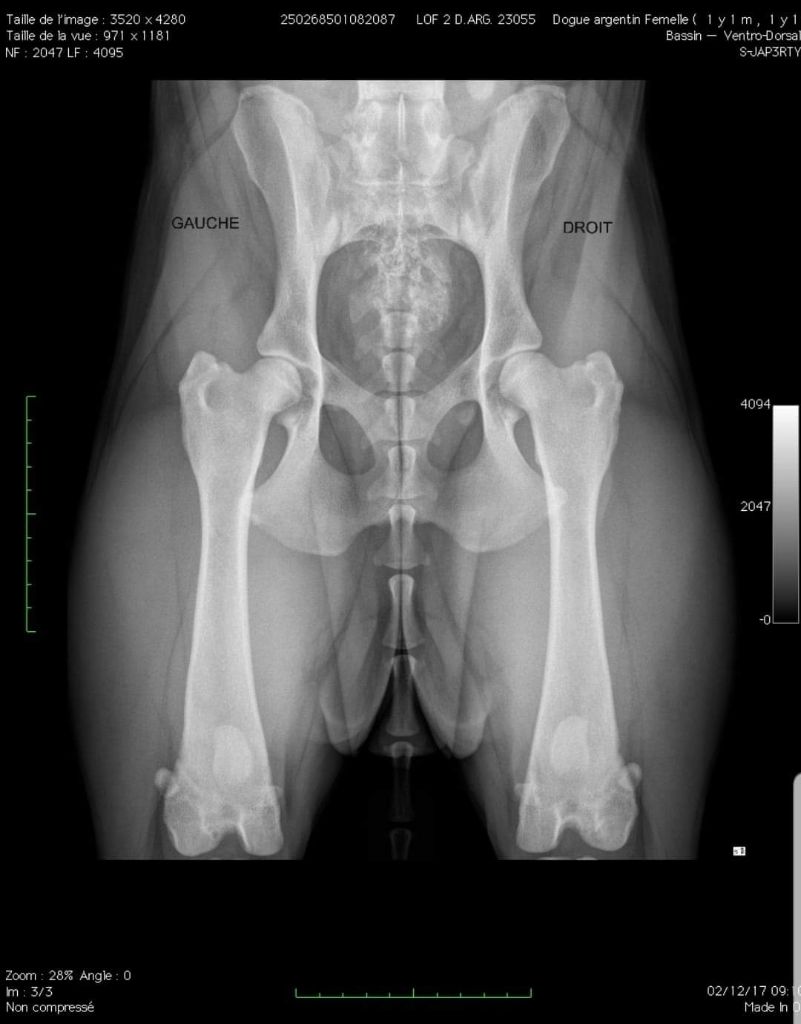

Dogo Argentino

Dysplasie A (lecture officielle FR).